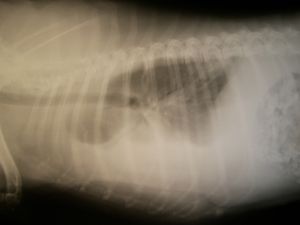

흉부 X선은 혈흉 진단에 이용되는 가장 흔한 검사이다.[63] 이상적으로 X선 영상은 바로 선 직립 자세에서 촬영해야 하나, 환자가 바로 선 자세로 있을 수 없다면 바로 누운 자세(앙와위)로 촬영할 수 있다. 직립 자세의 X선 영상에서 혈흉은 갈비가로막각이 커지거나(둔화되거나), 혈흉이 발생한 쪽 가슴에 방사선비투과성(하얗게 보이는 부분)이 부분적으로 또는 완전히 나타나는 소견을 보인다. 앙와위 영상에서는 혈액이 흉강에 고르게 퍼지는 경향이 있어, 가슴의 한쪽 절반이 다른 한쪽에 비해 흐릿하게 보이는 것으로 감지할 수 있다.[48] 수백 mL의 혈액은 직립 자세 영상에서 가로막과 배의 장기에 의해 가려질 수 있으므로 적은 양의 혈흉은 흉부 X선에서 놓칠 수 있다. 앙와위에서는 1L 가량의 혈액도 보이지 않을 수 있어 앙와위 영상의 민감도는 직립 영상보다 더 떨어진다.[64]